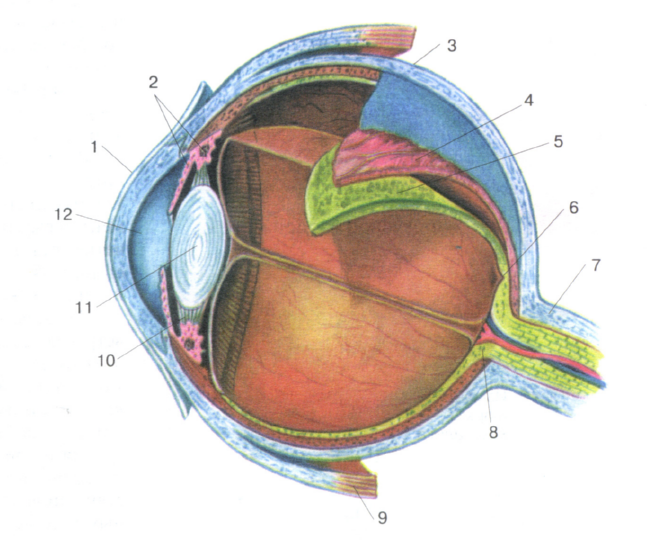

КТ-графики и изображение строения глаза